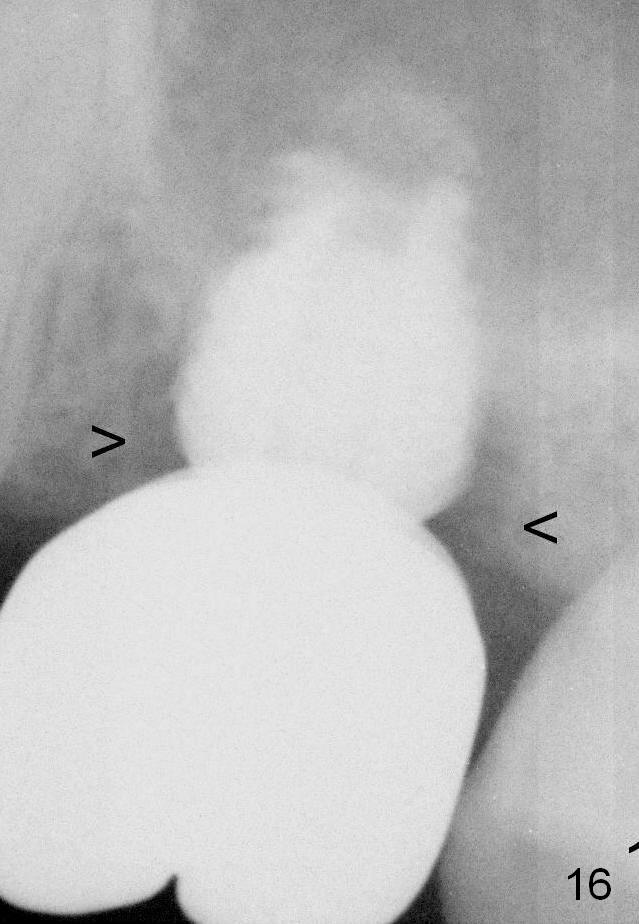

Although oral hygiene is pristine, there is apparent crestal bone resorption 12 months (Fig.16) and 20 months (Fig.17) post cementation, probably due to unfavorable crown/implant ratio and bruxism as well as pre-implantation bone loss (Fig.18,19).